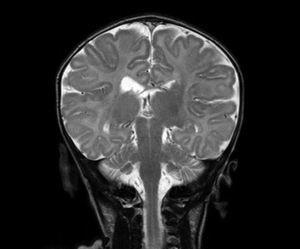

Se realizan las siguientes pruebas complementarias: radiografía de tórax donde se observa discreta cardiomegalia y signos de edema agudo de pulmón; ecografía abdominal (fig. 1) objetivándose un gran trombo que ocupa prácticamente toda la luz de la aorta abdominal desde la parte distal de la mesentérica superior hasta la bifurcación de ambas ilíacas. Ecografía transfontanelar: presencia de un trombo en el seno longitudinal superior, confirmado en la resonancia magnética (fig. 2) y en la angiografía cerebral (fig. 3) realizadas posteriormente.

Figura 1. Ecografía abdominal realizada a las 72 h del ingreso, donde se observa un gran trombo en la aorta abdominal.